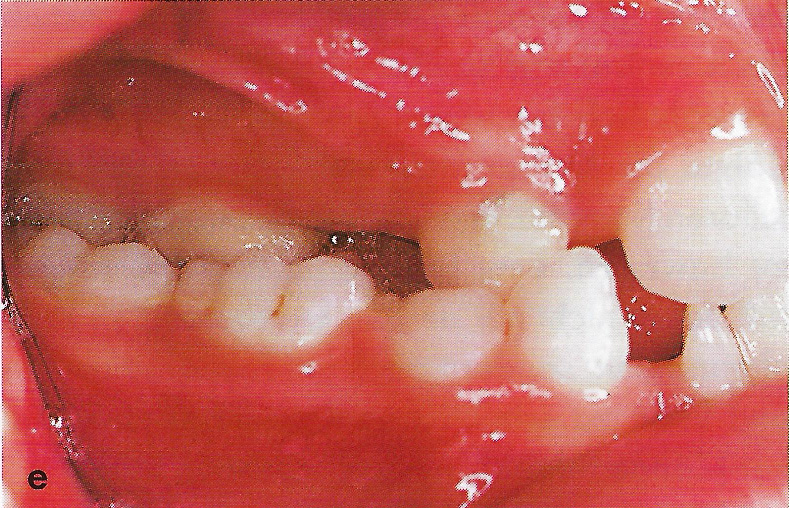

Abb. 1 a bis h Extra- und intraorale Ansicht der Patientin vor Behandlungsbeginn: Kopfbiß beziehungsweise umgekehrter Schneidezahnüberbiß und beidseitiger Kreuzbiß als Folge einer maxillären Hypoplasie sowie hälftenungleicher Mesialbiß infolge mandibulärer Verschiebung nach rechts.

• Ankylose Abb.1e

Diese Patientin war zu Behandlungsbeginn 7 Jahre alt. Sie hatte einen hälftenungleichen Mesialbiß infolge mandibulärer Verschiebung mit Kopfbiß beziehungsweise umgekehrter inzisaler Stufe, rechtsseitigem vollem Kreuzbiß und linksseitigem doppeltem Höckerbiß, maxillärer Kompression sowie Platzmangel in beiden Kiefern (Abb. 1 a bis h). Die kephalometrische Analyse ergab eine progene Kieferlagebeziehung, bedingt durch eine unterentwickelte Maxilla bei vertikalem Gesichtsschädelaufbau.